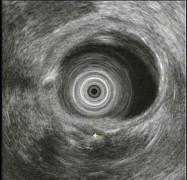

问题 女,55岁,腹痛便秘8年,大便干结伴排便不尽感,35天一次大便,无脓血便及恶心呕吐,食纳如常,体检无异常,结肠镜检查如图。患者哪种疾病可能性最大 ( )

选项 A、肠结核 B、溃疡性结肠炎 C、肠易激综合征 D、肠梗阻 E、结肠癌

答案 C